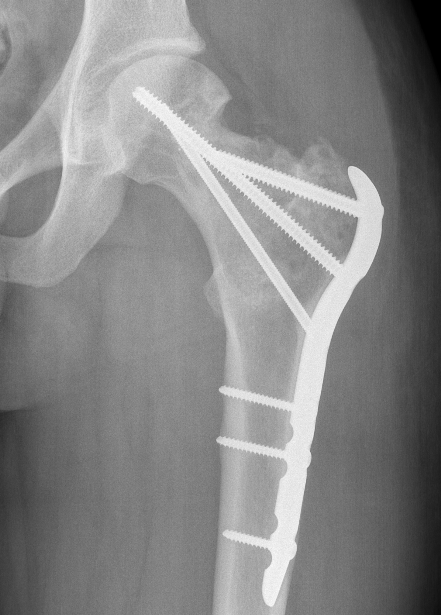

May allow surgical downstaging

- surgically unsalvageable / surgical treatment high morbidity

- arthrodesis or arthroplasty in young patients

Results

- prospective study of 20 patients with GCT

- pre-operative treatment with Denosumab

- pain relief in the first month

- improved radiological response with improved subchondral and cortical bone

- increased intra-lesional resection and joint preservation

- no effect on recurrence

Rutkowski et al Ann Surg Oncol 2015

- 222 patients at risk for wide resection treated with Denosumab

- allowed joint preservation in 96% of those thought to require joint replacement

- allowed joint preservation in 86% of those thought to require wide resection / arthrodesis

- recurrence rate 15%